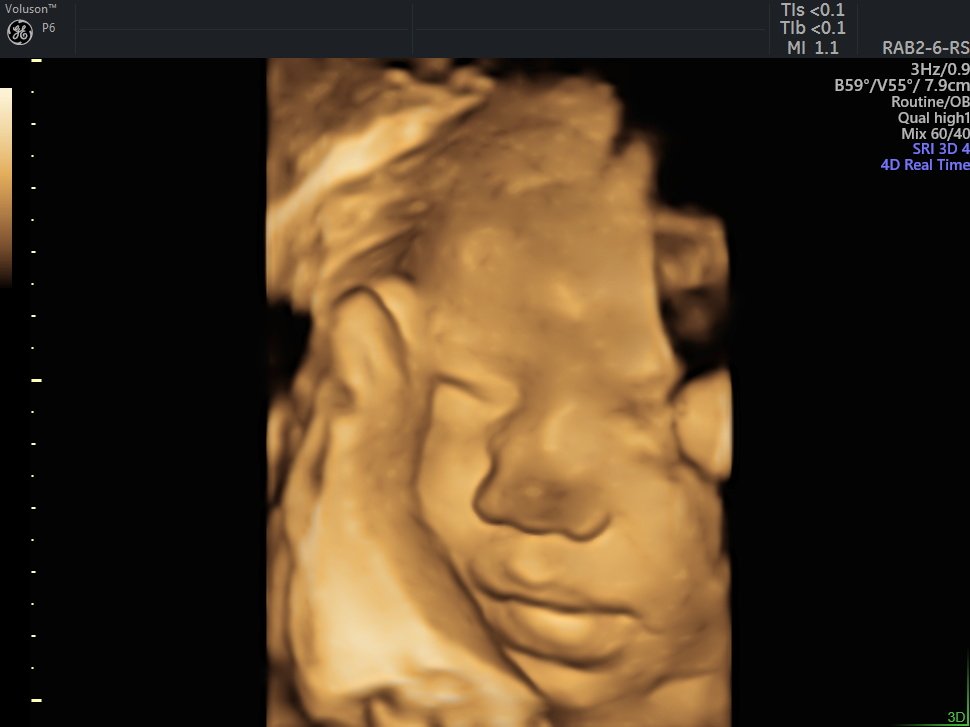

4 D Ultrasonografi

4 Boyutlu (Renkli) Ultrason ve Doppler Ultrasonografi